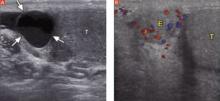

Order an ultrasound of the scrotum and testes, the accepted gold standard to highlight structural abnormalities of the testicles. The addition of color Doppler makes it possible to find areas of hypervascularity, an indication of inflammation in the testicle and epididymis (FIGURES 2A AND B).

FIGURE 2

Well-circumscribed extratesticular mass

In the image at left, ultrasound reveals an anechoic mass (arrows), representing either an epididymal cyst or spermatocele, superior to the testicle (T). A color Doppler image (right) reveals increased vascularity to the epididymis (E), as compared with the testicle.